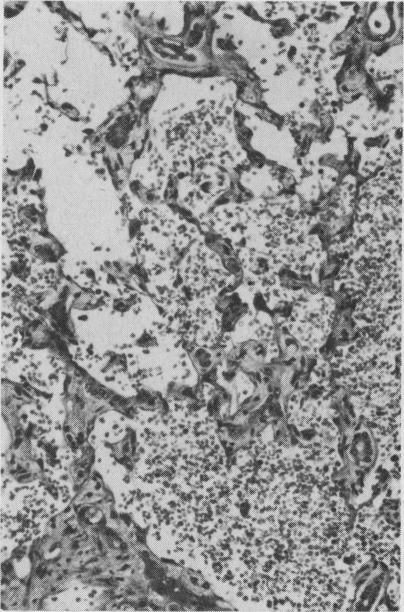

Histopathology of liver lesions associated with exposure to vinyl chloride monomer.与接触氯乙烯单体相关的肝脏病变的组织病理学

Proc R Soc Med. 1976 Apr;69(4):299-303. doi: 10.1177/003591577606900426.